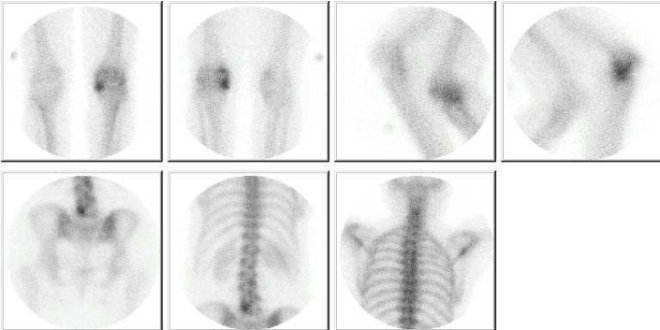

Vyšetření jsme provedli za 2 hodiny po i. v. aplikaci 700 MBq 99mTc oxidronátu (přípravek TechneScan HDP) na planární scintilační kameře MB 9200 opatřené HR kolimátorem v přední, zadní a bočních projekcích v poloze vleže. Jednotlivé snímky byly střádány po dobu 3 minut (obr. 1).

Obr. č. 1:  Statické scintigramy skeletu v přední, bočních a zadní projekci

Na jednotlivých scintigramech jsou patrná ložiska zvýšené osteoblastické aktivity v mediálním kondylu levé tibie, v levé části obratle L5.